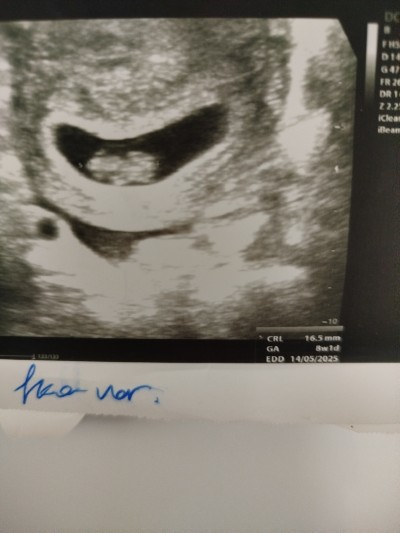

Merhaba 7+6 hamileyim geçen hafta 6+6 normal gününde çıkmıştı bugün 8+1 çıktı sorun olur mu

Gebelik haftası 7+6